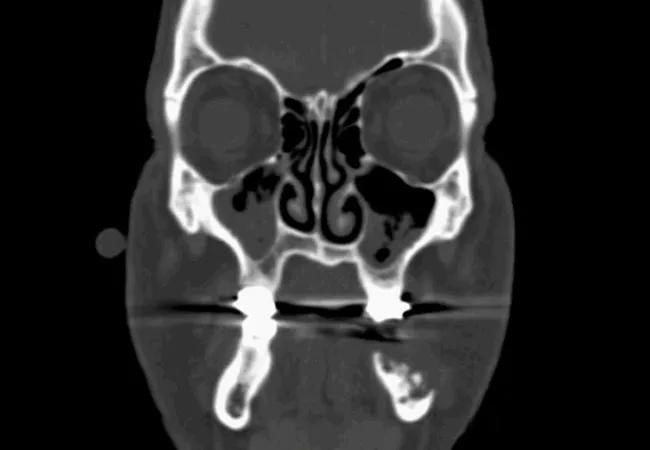

Osteoradionecrosis Scan